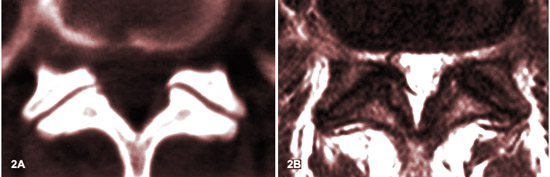

ARTHROSE FACETTAIRE (spondylarthrose) ET SON APPARENCE IRM :

LES STADES

Source: MR imaging and CT in osteoarthritis of the lumbar facet joints.